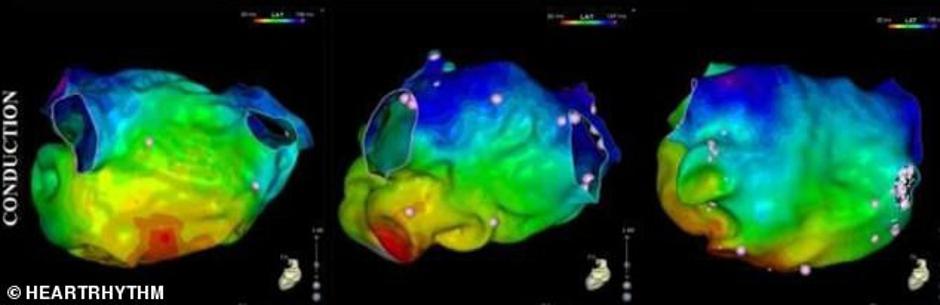

Skenovi srca, koje su snimili znanstvenici iz bolnice Alfred u Melbourneu, pokazuju kako električni impulsi putuju kroz atriju, mjesto gdje krv dolazi do srca. Podijelili su 75 ispitanika na kojima su bazirali ovo istraživanje u tri skupine; ovisno o tome koliko alkohola su rekli da konzumiraju. Inače, električni su impulsi ključni za rad srca jer ih kontroliraju čvorovi kojima su vezani za živčani sustav, a kojemu šalju informaciju kada se srce opušta a kada stišće.

U zdravom srcu oni slobodno i nesmetano putuju kroz zdravo tkivo, dok kod srca s oštećenim tkivom, zbog alkohola ili drugih faktora, impulsi ne hvataju taj signal na vrijeme (zbog čega srce ‘kasni’ sa preskakanjem).

Na skenovima je srce onih koji uopće ne piju svijetloružičaste boje koja pokazuje zdravo srčano tkivo kroz koje putuju impulsi. Srce onih koji ‘piju umjereno’ ima zakrpe u zelenoj boji, koja pokazuje mjesta na kojima su impulsi slabiji. Kao ‘umjerene konzumente’ su uzeli one koji piju između osam i 21 alkoholnog pića tjedno, točnije 14 u prosijeku.

Skenovi su tako dokazali da, kako je rekao i voditelj studije dr. Peter Kistler, čak i umjerena konzumacija alkohola može utjecati na impulse odgovorne za pravilan rad srca, a promjene koje se kod njih vide objašnjavaju zašto oni koji redovito piju često imaju problem sa srcem baš na mjestu gdje krv prolazi kroz njega.